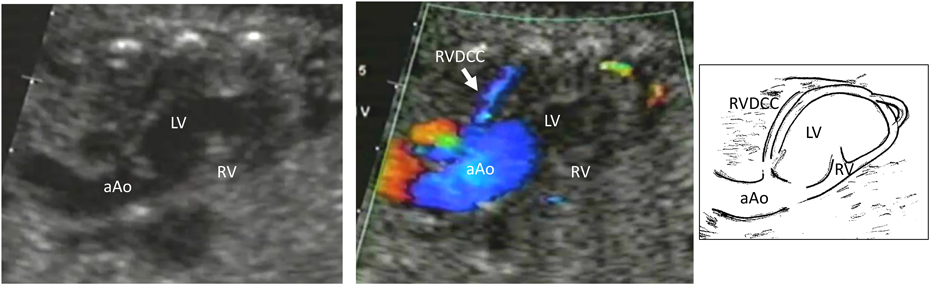

PA/IVSは肺動脈閉鎖に伴う右室低形成の程度により最終目標とする状態(Fontan循環,1.5心室修復,2心室修復)が異なるため,右心室の大きさや形態の確認を行う.三尖弁輪径と僧帽弁輪径の計測も有用である11).また類洞交通の有無と程度を確認する.類洞交通,とくに右室依存性冠血流(right ventricle dependent coronary circulation: RVDCC)の合併は出生後の予後に影響する12).(Fig. 4(video))また肺動脈閉鎖が膜様閉鎖かどうかも出生後の肺動脈弁形成術(バルーン治療もしくはBrock手術)適応に関わる.三尖弁閉鎖と同様に,卵円孔の形態や静脈管血流を確認することが生後早期BAS(balloon atrial septostomy)の必要性を評価する一助となりうる.